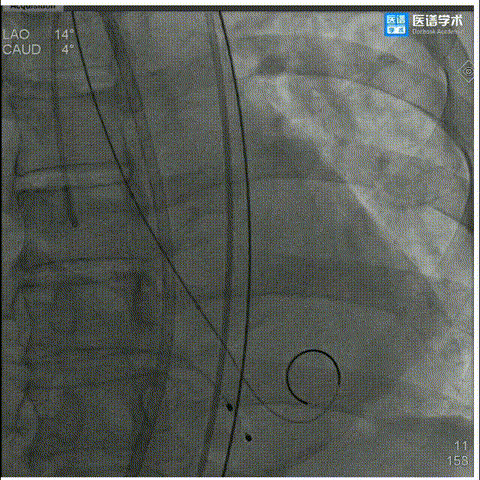

6.第一次释放瓣膜至工作位时,瓣膜下滑一个半菱形格,遂回收;后续为追求瓣膜释放最佳位置,多次半回收调整瓣膜至理想深度;

7.造影评估示瓣膜植入深度、工作形态良好、微量瓣周漏,遂予以全部释放;